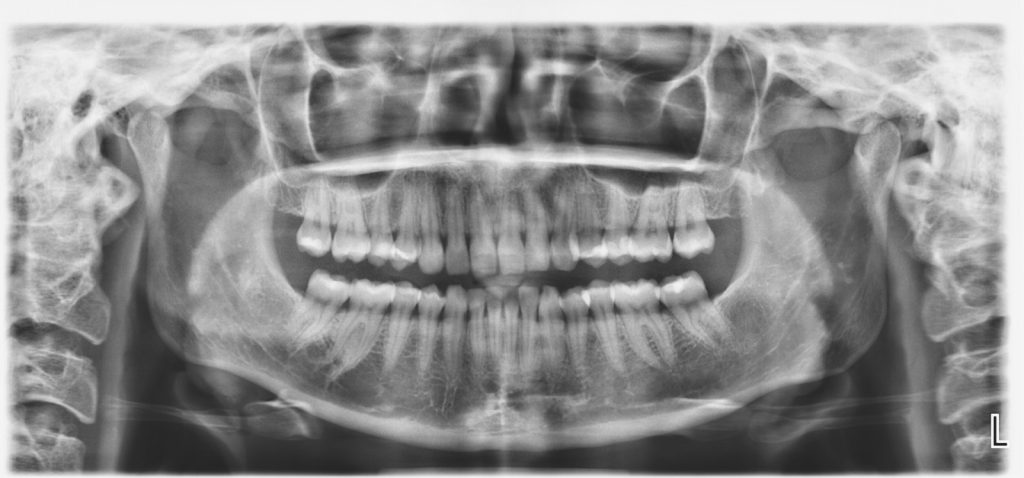

Digitalni ortopan

Panoramski 2D snimak kompletne gornje i donje vilice sa svim zubima i okolnim koštanim strukturama, temporomandibularnih zglobova i maksilarnih sinusa. Na ovom snimku se mogu videti i korenovi zuba, njihov položaj kao i zubi koji jos uvek nisu iznikli.  Izuzetno je važan u savremenoj dentalnoj dijagnostici i predstavlja zlatni standard za planiranje  lečenja i terapije.

Simanje zuba na digitalnom  ortopan aparatu  poslednje generacije traje kraće nego na klasičnim analognim aparatima, što samo snimanje čini udobnijim i komfornijim za pacijenta.  Snimci načinjeni na digitalnom aparatu su  mnogo boljeg kvaliteta i rezolucije a doza zračenja za samog pacijenta je višestruko  niža. Savremeni softver poslednje generacije nam daje mnogo mogućnosti i alata u obradi i dobijanju najboljeg mogućeg  snimka za svakog pacijenta ponaosob.

Svi snimci dobijeni u digitalnom formatu se mogu odštampati na film foliji, narezati na CD-u  ili poslati na e-mail ili viber.